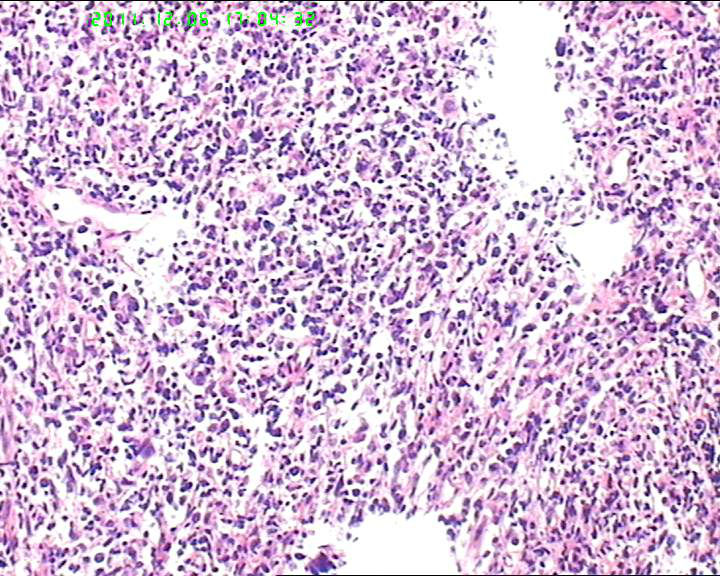

53岁女性患者,鼻腔肿物,中线恶网?韦格尔肉芽肿?

患者流脓涕1年,加重1月。左鼻腔息肉样增生物,质软,易出血。

送检灰白色绿豆大组织4块。

细胞异性明显,弥散分布,可见血管内皮异性明显,首先考虑血管肉瘤,恶黑,淋巴瘤?

组织内见大量形态各异的异型明显的细胞,弥漫分布,背景见肿瘤素质,首先考虑结外NK/T细胞淋巴瘤,鼻型;恶黑待排。